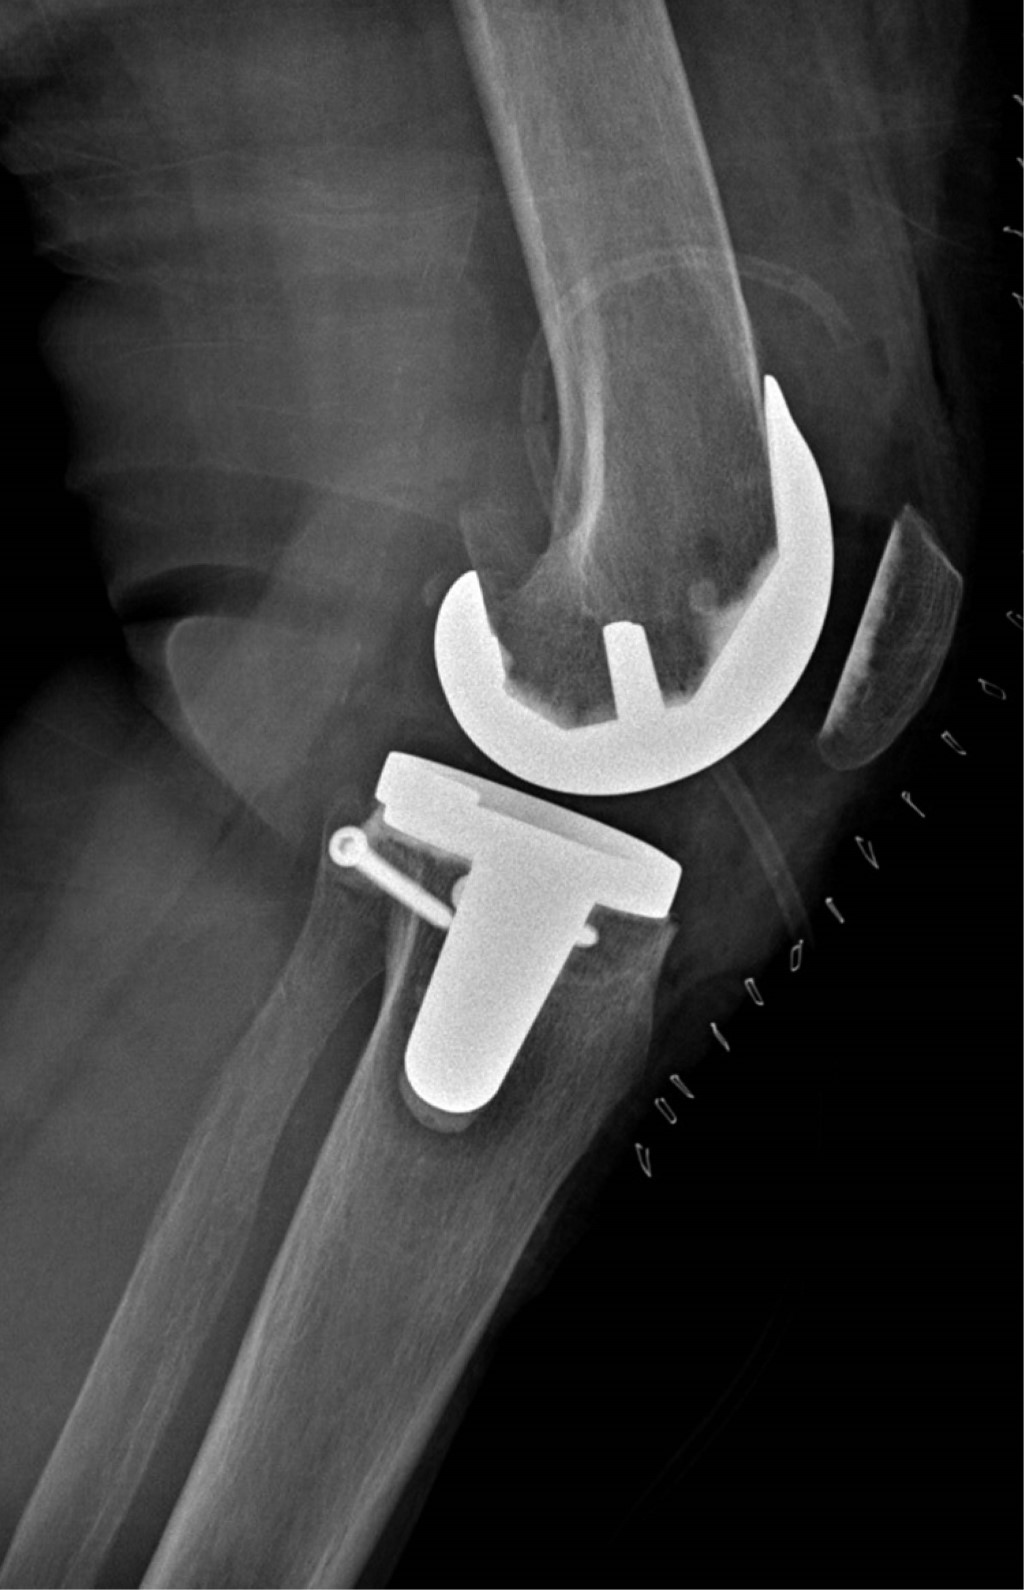

Se realiza abordaje anterior a rodilla izquierda con artrotomía transvasto, luxando patela sin eversión, hacia lateral, se retiran osteofitos femorales y ligamento cruzado anterior y posterior, y se realiza corte femoral distal con valgo de 7o, posteriormente realizando corte tibial en 0o. Se mide tamaño de plantilla femoral, siendo de tamaño 5, y se realizan cortes anteriores, posteriores y chaflanes en fémur con 3o de rotación externa. Se visualiza defecto tibial de 5 mm de profundidad (Figura 4) y se regulariza borde con sierra para hueso, obteniendo lecho plano y sangrante, adecuado para colocación de injerto. Se recupera bloque de hueso para injerto proveniente de osteotomía de corte femoral y se coloca en zona de defecto tibial realizando osteodesis con clavos Kirschner de 1.6 mm (Figura 5). Después se coloca nuevamente plantilla de corte tibial y se regulariza altura de injerto con sierra, procediendo a fijación definitiva con tornillos de esponjosa 4.0 mm de rosca completa con dirección de medial a lateral, cuidando no invadir espacio metafisario central para colocación de implante tibial. Se introduce espaciador de 10 mm en espacio tibiofemoral y se realiza balanceo de tejidos blandos con técnica de pie crusting sobre estructuras mediales hasta obtener gaps simétricos en flexión y extensión. Se mide tamaño de componente tibial, siendo de tamaño 3, y se determina rotación adecuada alineando punto medio de plantilla con la unión del tercio medial con tercio medio de tuberosidad tibial anterior, después se realiza perforación metafisaria, sin interferencia de tornillos de fijación de injerto. Se coloca plantilla de prueba y se procede a medir y realizar corte patelar para componente de tamaño 38 con medialización de componente. Se verifica adecuada movilidad y estabilidad, retiro de componentes de prueba, se coloca isquemia, irrigación de lecho quirúrgico, sellado interfase entre injerto y metáfisis tibial con cemento y se procede a colocar implantes definitivos cementados, con inserto 10 posteroestabilizado (Figuras 6 y 7). Se verifican rangos de movimiento alcanzando flexión de 130o y extensión de 0o, con adecuado balanceo de tejidos blandos, después se cierra por planos hasta piel.

La paciente es egresada al día siguiente de procedimiento quirúrgico con indicación de mantener extremidad pélvica izquierda en descarga hasta encontrar datos radiográficos de consolidación en injerto, y se cita a revisión a los siete, 14 y 28 días después del procedimiento (Figuras 8 y 9).

En el caso aquí reportado, se utilizó injerto autólogo proveniente del corte de chaflán anterior femoral para la reconstrucción tibial medial, el cual se fijó con tornillos de esponjosa de 4.0 mm, sin encontrar datos de reabsorción, aflojamiento o fragmentación en un seguimiento temprano de ocho semanas, con mejoría significativa de sintomatología y aumento de funcionalidad (Figuras 10, 11 y 12).